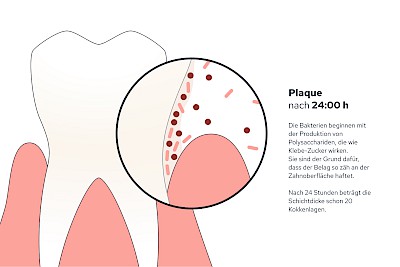

Plaque (Biofilm)

Als Plaque bzw. Biofilm bezeichnet man die Gesamtheit aller Mikroorganismen (Mikrobiom) auf der Zahnoberfläche. Werden die Zähne nicht geputzt, haften die Beläge nach 24 Stunden bereits so fest, dass diese mit der Zahnbürste schon nicht mehr vollständig entfernt werden können.